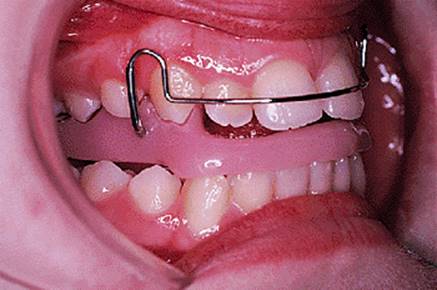

The appliance holds the mandible in a forward postured position, in this case with the incisors edge to edge (Fig. 18.1(f)). The facial musculature is thus stretched, and applies a posterior force to the upper arch and an anterior force to the lower arch. The lower incisors have acrylic capping to prevent excessive labial tilting of the lower incisors, and this also serves as a bite-plane to reduce the overbite (Chapter 10). The appliance must be worn for at least 14–16 hours each day, but once the overjet has been reduced fully the amount of daily wear can gradually be reduced to sleeping hours only. The patient should continue to wear the appliance overnight in this way as a retainer, at least until the period of rapid pubertal growth is complete. Figures 18.1(g) and 18.1(h) show the dental and facial changes which occurred during treatment.

Fig. 18.1. (a) This 12-year-old girl had a skeletal II facial pattern and average facial proportions. The lips were incompetent with the lower lip lying below the upper incisors at rest. (b), (c) She had a Class II division 1 malocclusion with an overjet of 10 mm, the overbite was increased and complete, and the molar relationship was Class II on both sides. (d), (e) The upper and lower arches were well aligned. (f) A functional appliance (an activator) was fitted. (g) The corrected occlusion with Class I incisor and molar relationships. (h) The patient's facial profile at the end of treatment.

18.5.1. The Andresen activator

There are many variations upon Andresen's original design. An Andresen activator is shown in Fig. 18.5. It is a monoblock design, that is to say it comprises upper and lower acrylic appliances fused together. The original design had a solid palate, but that shown has been made with an open palate to reduce its bulk. The lower incisors are capped to minimize the tendency for them to procline during overjet reduction, and which also serves as a bite-plane to reduce the overbite. The capping resists tipping of the teeth so that any labial movement will have to be bodily translation and is therefore minimized. The labial bow lies passively against the upper incisors, and the palatal wire is again intended to minimize palatal tilting of the upper incisors.

Fig. 18.5. Andresen activator used to treat the patient shown in Fig. 18.1.